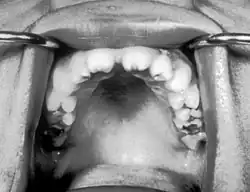

In 45–65 % der Fälle weisen dabei die bleibenden oberen mittleren Schneidezähne eine typische tonnenförmige Gestalt mit einer halbmondförmigen Einkerbung des Zahnrandes auf, in 22–65 % der Fälle sind die ersten bleibenden Molaren (Sechsjahrmolar) betroffen, die dabei eine "maulbeerförmige" Gestalt aufweisen.

Hinzu kommt ein lückiges Gebiss (Diastemata), wobei die Zähne oft zur Mitte hin konvergieren.[1]